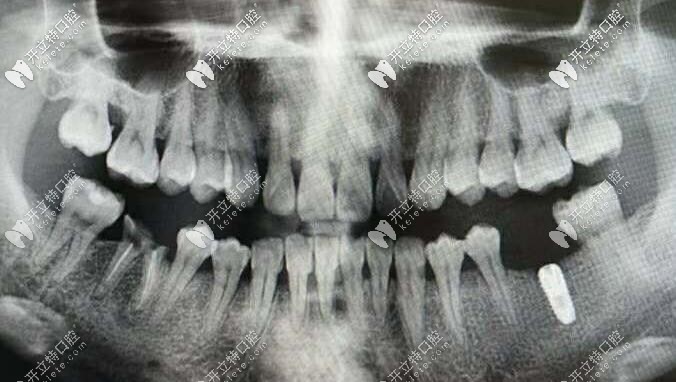

韓國(guó)inno種植體

韓國(guó)伊諾種植體種植體在近幾年內(nèi)慢慢進(jìn)入市場(chǎng),一經(jīng)使用便受到了廣大顧客的一致認(rèn)可。伊諾種植體是經(jīng)過(guò)了FDA、CE、CFDA等認(rèn)證的種植體,不管是安全性還是性能方面,都有著不錯(cuò)的表現(xiàn)。

首先從材質(zhì)上看,inno種植體采用的是四級(jí)純鈦材質(zhì),尤其是自主研發(fā)的 Modi—ASD(改性陽(yáng)極氧化鈦)表面處理技術(shù),以其超親水和的骨結(jié)合效果令種植手術(shù)更加安全、穩(wěn)定。

這個(gè)材質(zhì)還有一個(gè)好處那就是——具備超親水特性及快速的骨結(jié)合速度。對(duì)于臨床病例如即刻植入、 即刻負(fù)重、上頜竇提升、植入深度調(diào)整都具有優(yōu)勢(shì)。

其次伊諾種植體還有多種不同的型號(hào),比如常規(guī)、超短、超窄、迷你(一段式)種植體,以及多樣化修復(fù)基臺(tái),能滿足口腔的各種修復(fù)需求。